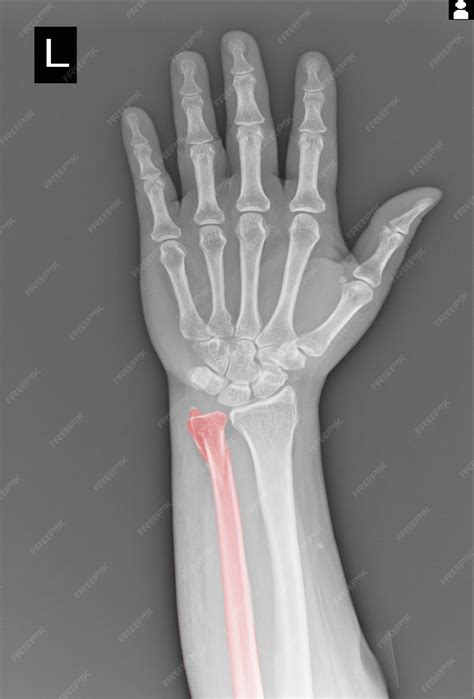

• Distal Radius Fractures: These affect the end of the radius bone in the forearm, near the wrist. They are common in falls and can be quite painful.

Each type of fracture may require a different approach to treatment, so accurate diagnosis through a broken hand x-ray is crucial.